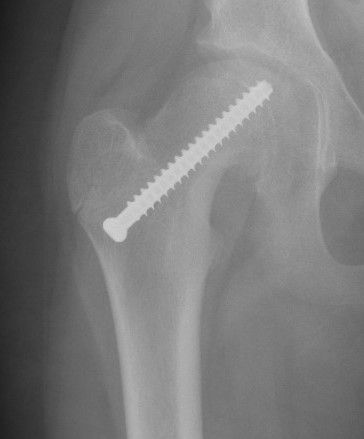

Intertrochanteric / Southwick

Technique

Removal anterolateral bone wedge below lesser trochanter

Valgising / flexion / internal rotation

Base of neck / Kramer

Closing wedge anterior and superior